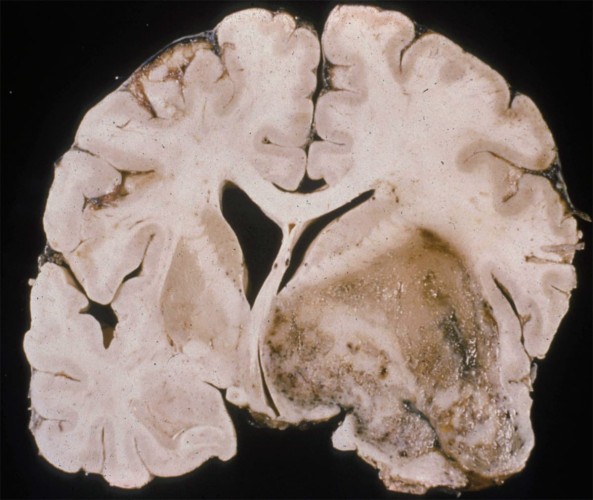

- Imaging: Contrast ring-enhancing lesions with significant vasogenic edema. Lesions can also have internal necrosis and can extend through the corpus callosum (butterfly lesion).

- Pathology: Cells with increased mitotic activity with pseudopalisading necrosis and microvascular endothelial proliferation.